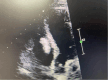

We report a case of intracardiac cement embolism in a 24-year-old male patient as a rare postprocedural complication of percutaneous vertebroplasty. The patient was assessed 1 month after the procedure because of persistent tachycardia. Computed tomography scans showed an intracardiac mass in both the right atrium and right ventricle. After thorough multidisciplinary discussion, the patient was subsequently managed conservatively in conjunction with serial imaging and close surveillance.